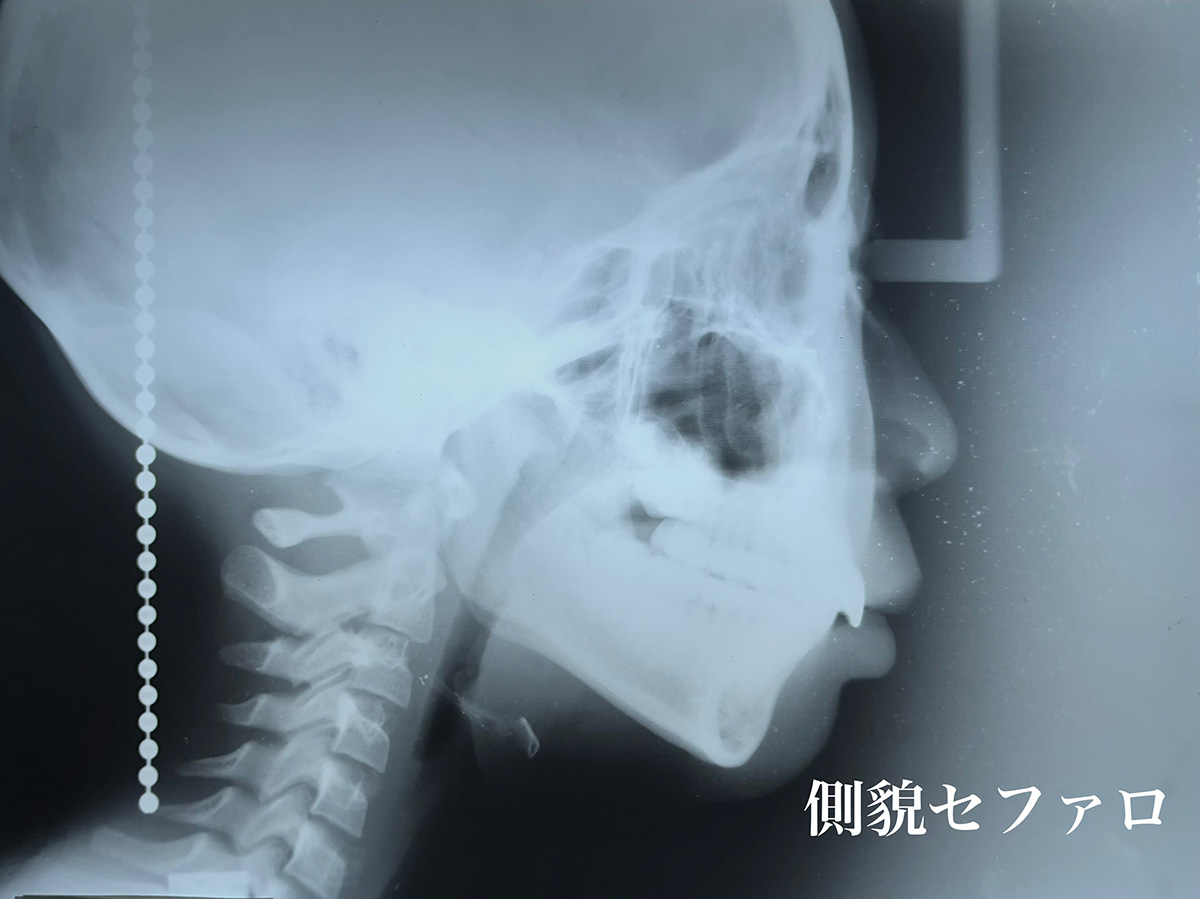

徹底した診査診断

私の矯正歯科治療の診査診断のための資料収集は、独特の手法です。 患者さんは、常に私の側に居られる訳ではありませんから、治療方法が決定するまで患者さんの治療に必要な資料を徹底的に収集することは、とても大切なことです。 私は平行模型と呼ばれる歯型の石膏模型を使用しません。 なぜなら、歯並びと頭蓋骨の位置的関係が、その平行模型には全く反映していないからです。私はロバート.リー博士の咬合理論を継承しております。 ですから、パナデント咬合器に患者さんの歯型模型を装着して、咬み合わせ診断、顎関節の頭蓋骨との位置的関係の診断し、初めて歯列の改善を進めてまいります。

私の矯正歯科治療は【スタイナーの分析】を基にアレンジした治療方法です。矯正歯科治療は、もともと【見栄え】の改善を目的に進歩発展してきた歴史があります。 そこに大きな問題が在ると私は考えておりました。歯並びを変える治療は、全顎的治療、すなわちオーラルリハビリテーションと言えます。生理的な正常咬合と審美的な歯並びの調和なくして【治療咬合】とは言えません。 エッジワイズ メカニズムを駆使して、【治療咬合】を創り、審美的満足を患者さんに実感していただきながら、治療が終了したあとの時間の経過と共に【生理的咬合】へと移行してゆくという自然体への誘導が、私【畑テクニック】の特徴と考えています。